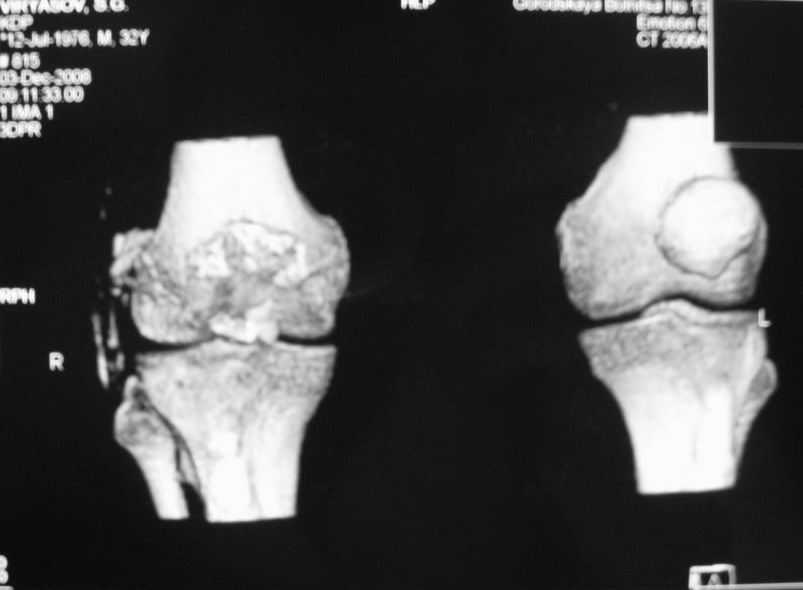

Уважаемые коллеги! Обратился пациент 32 лет с травмой коленного сустава от июля 2008 года - падение с мотоцикла, прямой удар передней поверхностью коленного сустава. Диагноз - открытый оскольчатый перелом надколенника. В одной из больниц города выполнили ПХО, шов надколенника лавсаном. Заживление раны с частичным нагноением(разведена на участке 3 см).Сейчас мягкие ткани в порядке. R-снимки, КТ в приложении. Объем движений 0/0/110 гр.Ходит почти без хромоты. Жалобы на торчащий под кожей один из отломков, боль в этой точке. Вопрос: что делать? Первое - убрать этот отломок и на этом закончить. Второе - оставить все как есть(отломок не так уж и сильно мешает). Ждать возможного развития артроза, дальше по ситуации. Третье - подумать о протезировании надколенника.

Судя по фото, объём движений достаточный, деформация стрктур колена, визуально, тоже не очень выражена. Развитие артроза в сегодняшнем состоянии и после протезирования прогнозировать дело неблагодарное. Так что может действительно решить те вопросы и неудобства, которые на сегодняшний день беспокоят пациента, а далее осуществить динамическое наблюдение (протезирование надколенника никуда в принципе не уйдет). Просто в жизни бывают ситуации когда поговорка "лучшее враг хорошего", актуальна. С уважением Михаил.